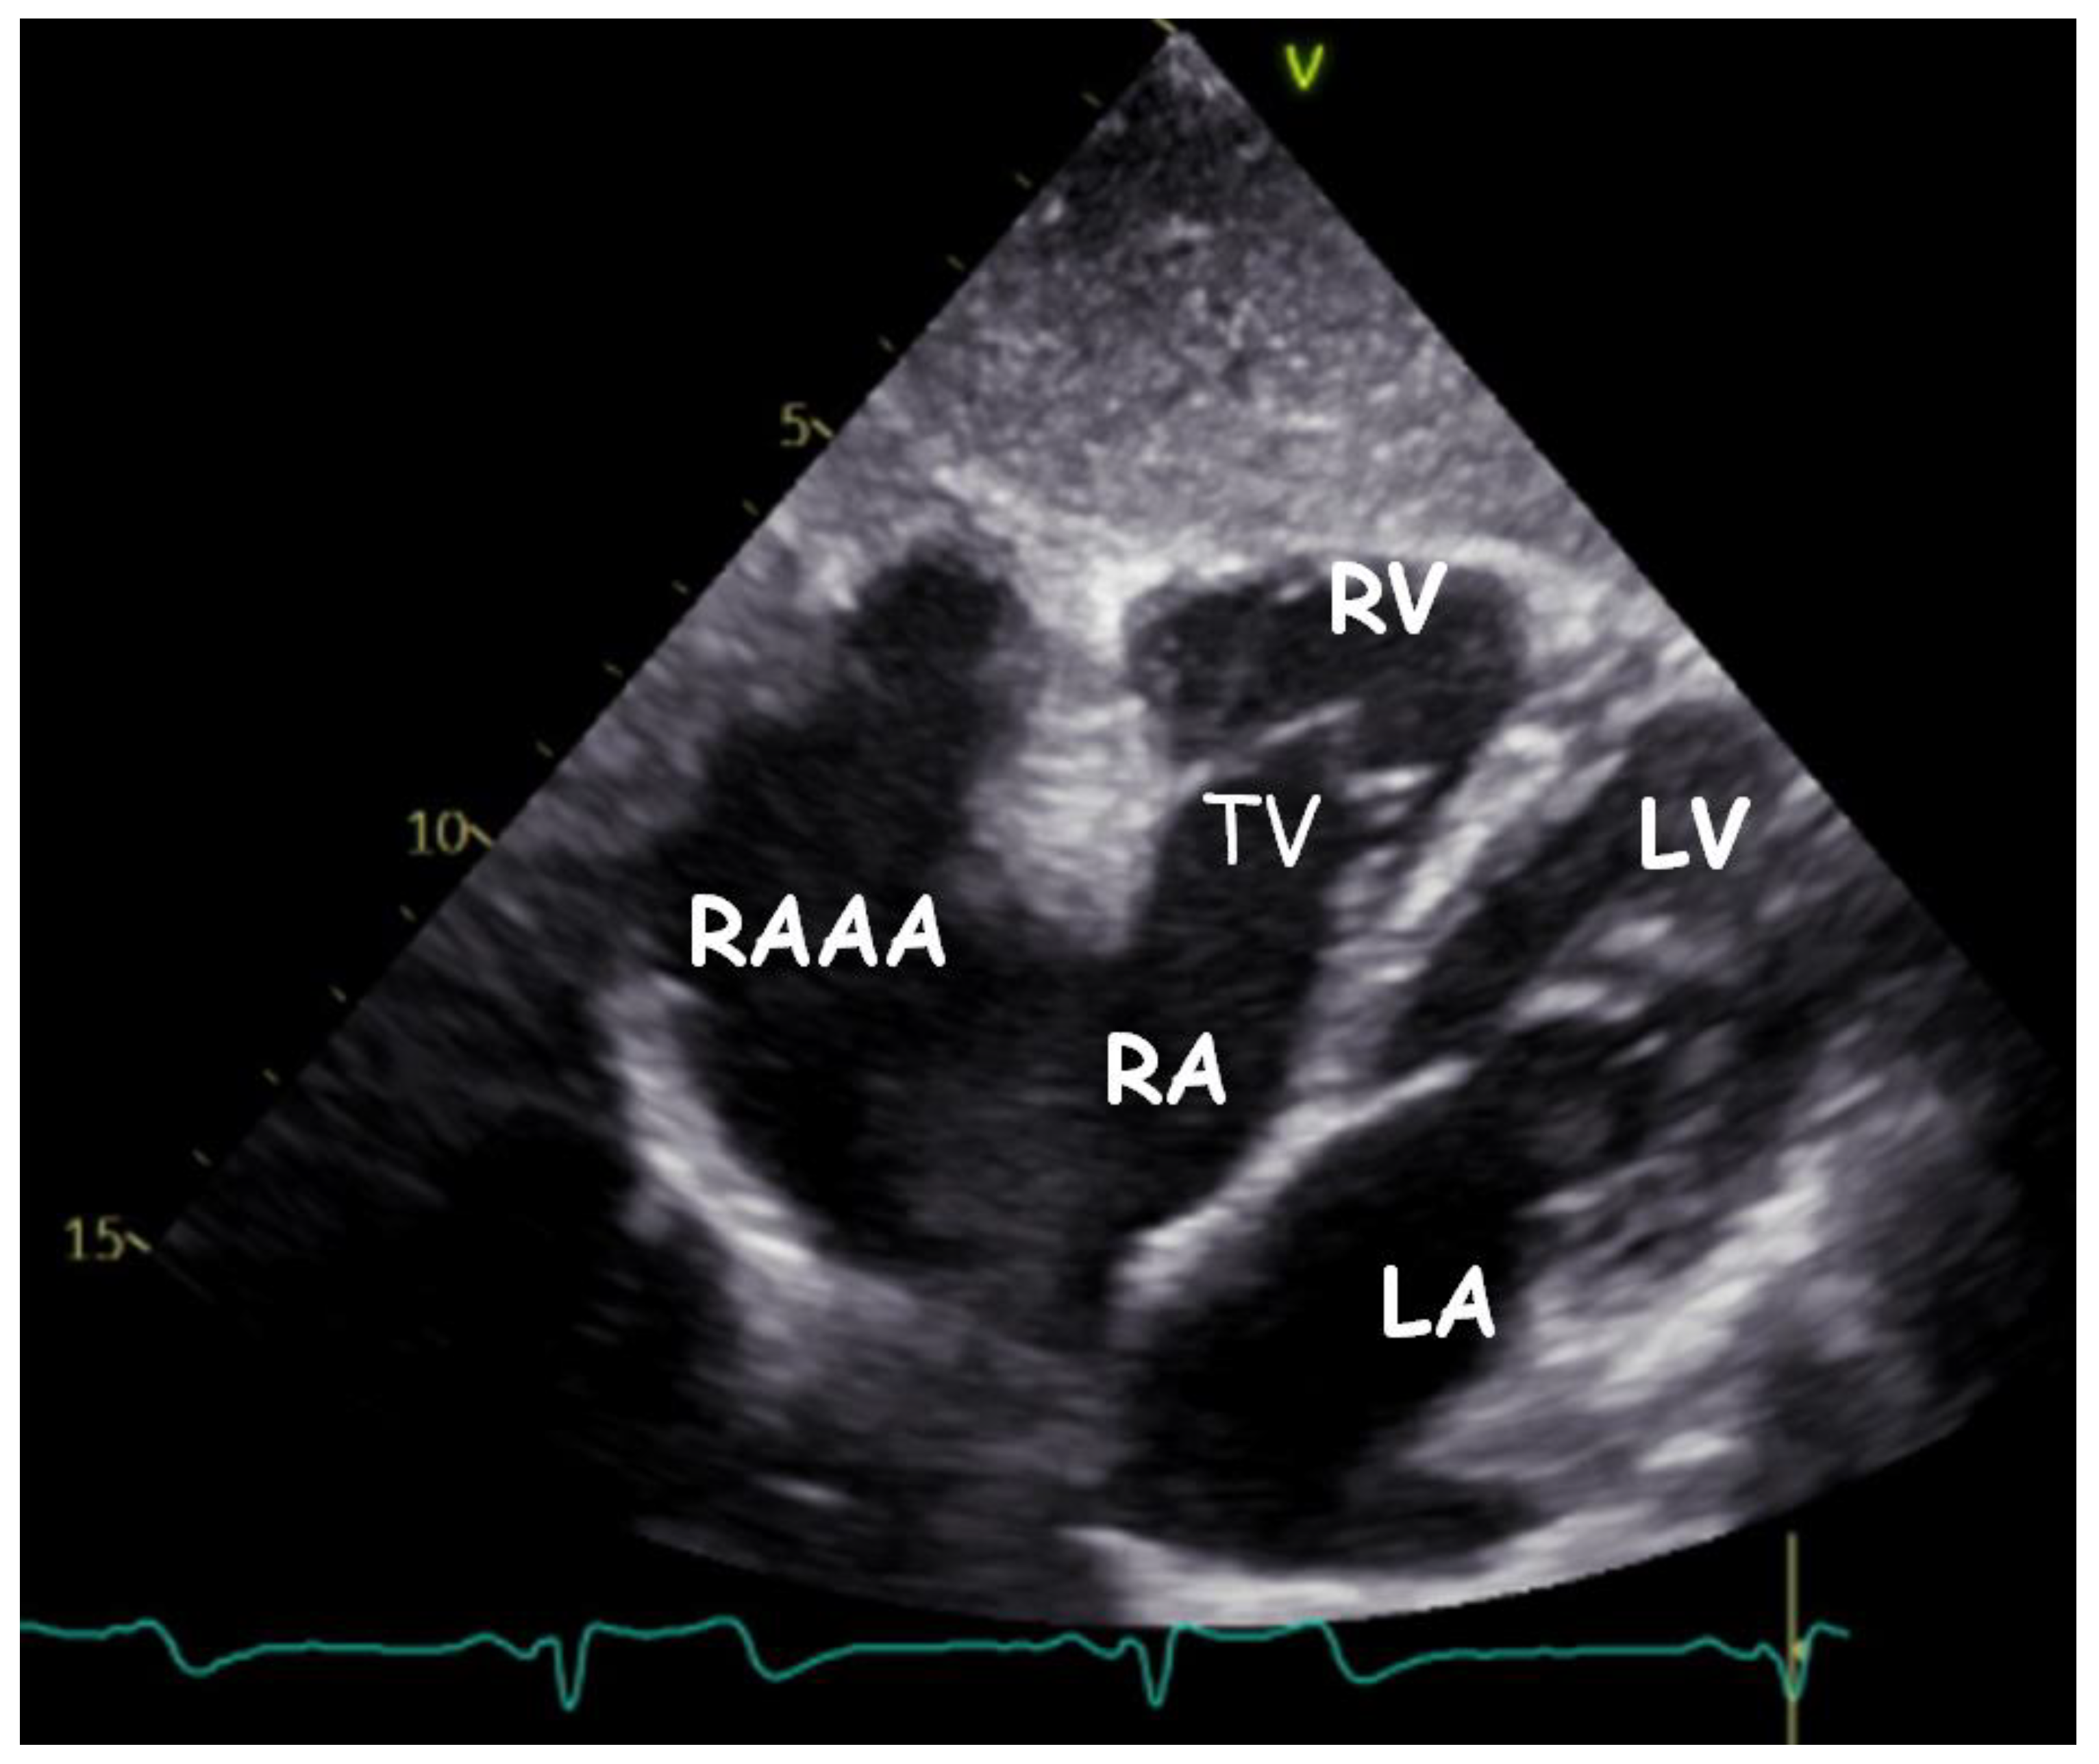

| RAAA | Right Atrial Appendage Aneurysm |

| RAA | Right Atrial Appendage |

| RV | Right Ventricle |

| RA | Right Atrium |

| LV | Left Ventricle |

| LA | Left Atrium |

| TV | Tricuspid Valve |